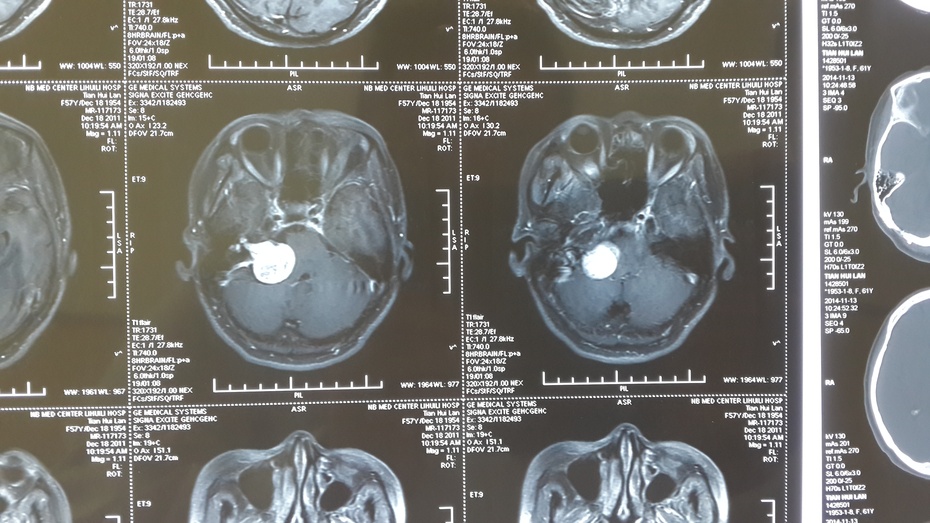

西安交通大学第一附属医院王拓教授团队听神经瘤病例汇报

图片尺寸1613x1210